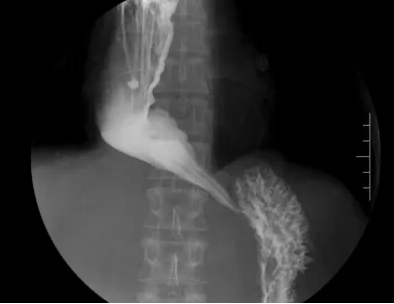

术后碘水造影

6月24日,李俊主任为患者顺利实施全麻气管插管下经口内镜下肌切开术(POEM),耗时近2小时,术后禁食48小时,予以抑酸护胃、预防性抗感染、营养支持等治疗,复查上消化道碘水造影见食管下段及贲门已扩张,造影剂通过顺畅、食管扩张较术前减轻,未见造影剂漏入隧道或其他部位,患者开放流质饮食后进食顺畅。目前患者已恢复出院。